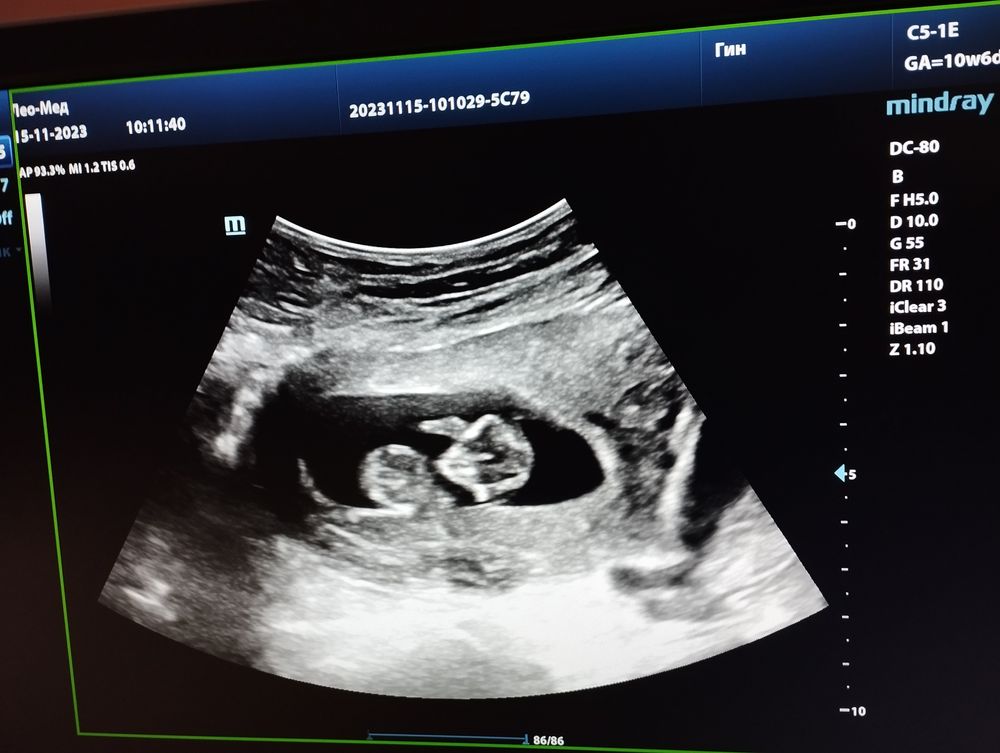

Мы с узи! 🥰💕

Как здорово!)) а какой размер ктр крохи?)

Софья, ктр 49)

Елена, богатырь наверное растет!))) мне послезавтра на узи в 10+1 и тоже интересно сколько уже ктр) в 9+2 был ктр 24мм. Сегодня вот доплером сердечко слушала))

Софья, наверное богатырь точно) у меня все дети маленькие, я сегодня аж опешила, когда узистка сказала 🙈 Про доплер тоже долго думала, но что то решила не брать) тут уже скрининг скоро, потом пол узнавать пойду, так и пролетят недели)

Елена, ого, какие вы большие для своего срока) опережаете)) поздравляю)) врач-узи в жк и видео сняла мне и отправила) каждый день смотрю, как он барахтается, ручкой машет🥰

Елена,У меня в 12-13 недель ктр был 61мм,почти на неделю опережала на первом скрининге,на втором скрининге срок ровно как по мес.Врач мой считает как по первому скринингу 25-26 недель на данный момент.Чсс был 168

Какие замечательные новости с утра! 😍 Такой милый лапусик))) видимо, будет крупненьким. Пусть растёт здоровым!🙏❤ Очень похож на мальчика, удивлюсь, если окажется, что это девочка🤭

Катюнечка Солнышко, я тоже в уверенности что мальчик) с самого начала беременности) не знаю почему)))